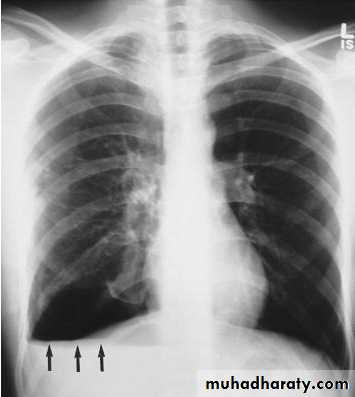

• Alveoiar oedema (‘Bat’s wings’)

• Kerlev B lines (interstitial oedema)

• Prominent upper lobe vessels

• Cardiomegaiy

• Pleura

• effusion

Kerley A lines (Arrows), Kerley B lines (arrowheads)